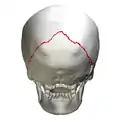

Lambdoid suture (shown in red line) | |

The lambdoid suture (or lambdoidal suture) is a dense, fibrous connective tissue joint on the posterior aspect of the skull that connects the parietal bones with the occipital bone. It is continuous with the occipitomastoid suture.

The lambdoid suture is between the paired parietal bones and the occipital bone of the skull. It runs from the asterion on each side.

The lambdoid suture is named due to its uppercase lambda-like shape.

Parietal bones (above) and occipital bone (below). Skull seen from behind. Showing Λ-like shape of the lambdoid suture.

Skull seen from behind. Showing Λ-like shape of the lambdoid suture. Lambdoid suture seen from above.